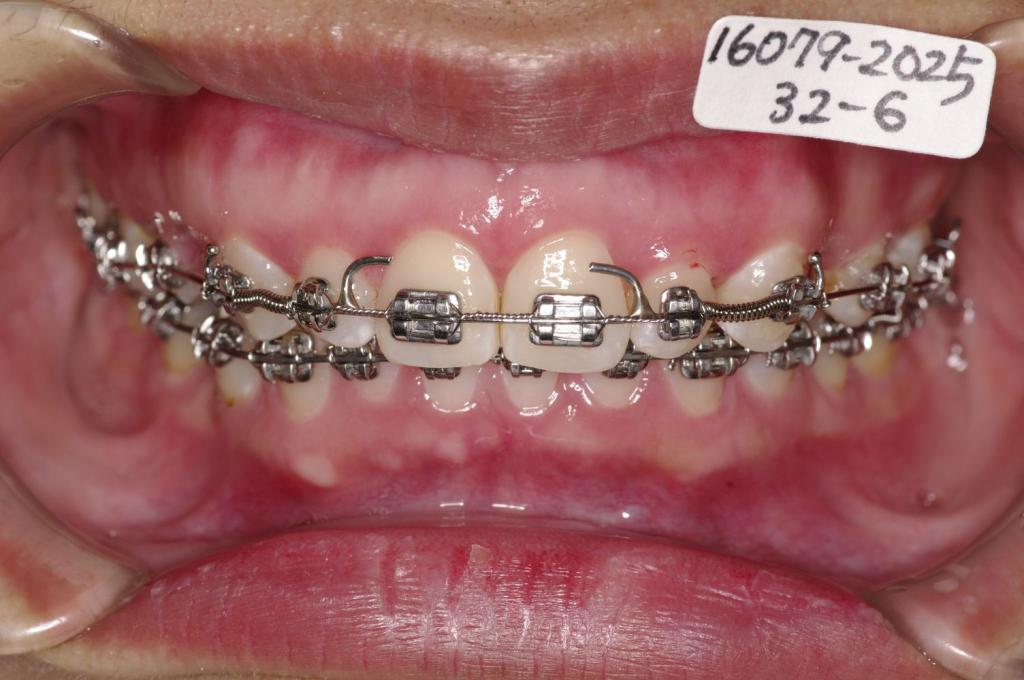

- 前歯、出っ歯・開咬の矯正治療

- 出っ歯